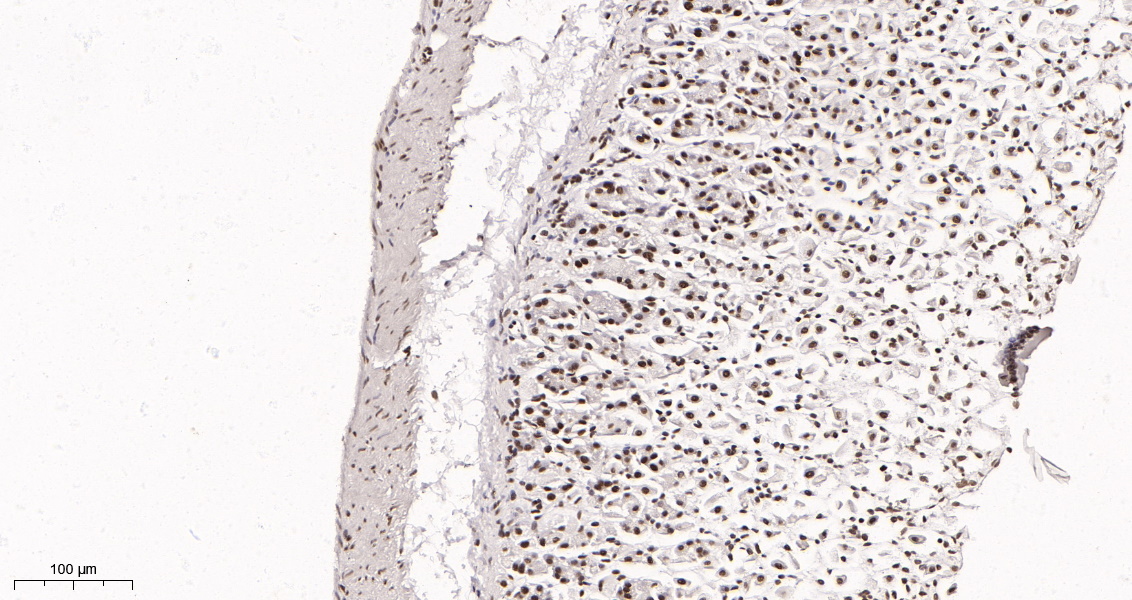

产品名称Rad21 (16H8) Rabbit Monoclonal Antibody

推荐应用WB,IHC-P,IF-P,IF-F,IF-ICC,IP,ELISA

稀释度IHC-P 1:200-1000,WB 1:1000-5000,IF-P/IF-F/IF-ICC 1:200-1000,ELISA 1:5000-20000,IP 1:50-200

背景介绍The protein encoded by this gene is highly similar to the gene product of Schizosaccharomyces pombe rad21, a gene involved in the repair of DNA double-strand breaks, as well as in chromatid cohesion during mitosis. This protein is a nuclear phospho-protein, which becomes hyperphosphorylated in cell cycle M phase. The highly regulated association of this protein with mitotic chromatin specifically at the centromere region suggests its role in sister chromatid cohesion in mitotic cells. [provided by RefSeq, Jul 2008].